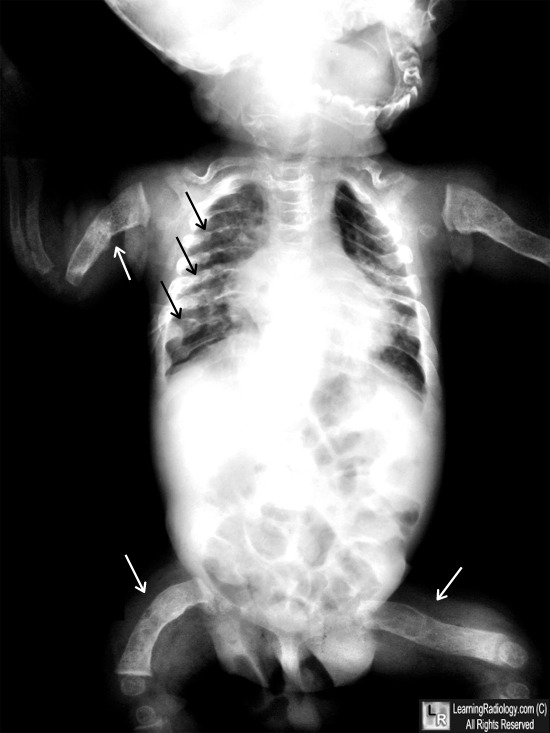

From www.learningradiology.com

LearningRadiology Brittle Bones Xray Signs and symptoms may range from mild to severe. Osteoporosis causes bones to become weak and brittle — so brittle that a fall or even mild stresses such as bending over or. Osteogenesis imperfecta (oi), also known as brittle bone disease or brittle bone dysplasia, most commonly presents in children. Osteogenesis imperfecta (oi), also known as brittle bone disease, is. Brittle Bones Xray.